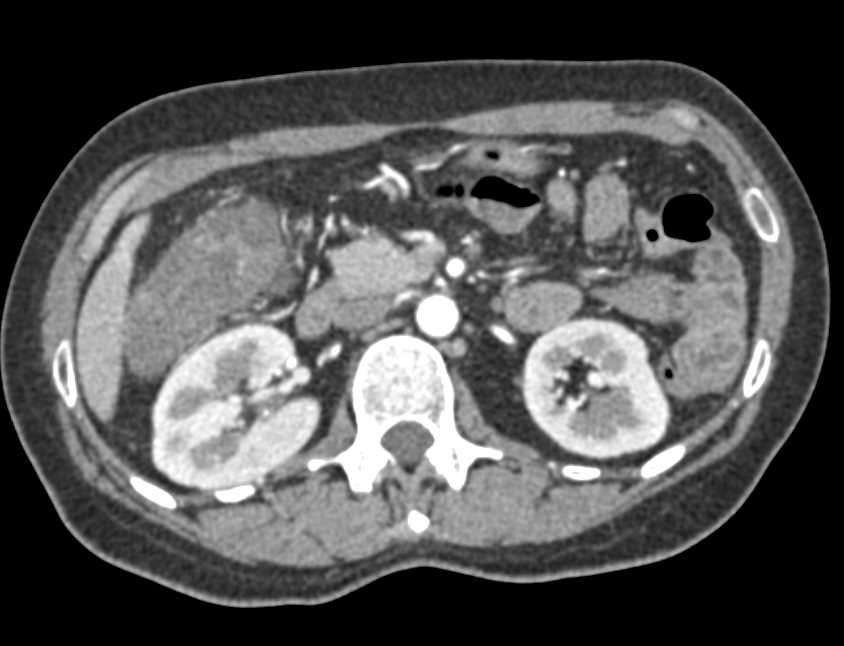

Metastatic Carcinoid Tumor with Implants on Liver and Diaphragm